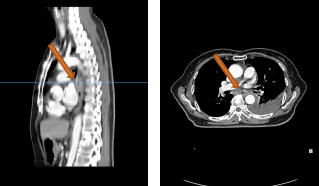

2022-03-28 PET-CT:1、食管癌放化疗后,食管胸中段管壁不规则增厚伴结节状代谢增高,与上次(2021-10-28)PET/CT检查对比,病灶代谢较前明显增高,考虑为肿瘤复发病灶。2、左肺癌放疗后及靶向药治疗后,原左肺上叶团块状高代谢“肿瘤灶”,现范围较前稍缩小,代谢较前稍减低,考虑为治疗后改变(肿瘤完全活性受抑,伴少许炎性反应可能)。

复发诊断:

1、食管鳞状细胞癌cT3N0M0 IIb期综合治疗后复发rT3N0M0 IIb期

2、左肺腺癌cT3N0M0IIb期综合治疗后